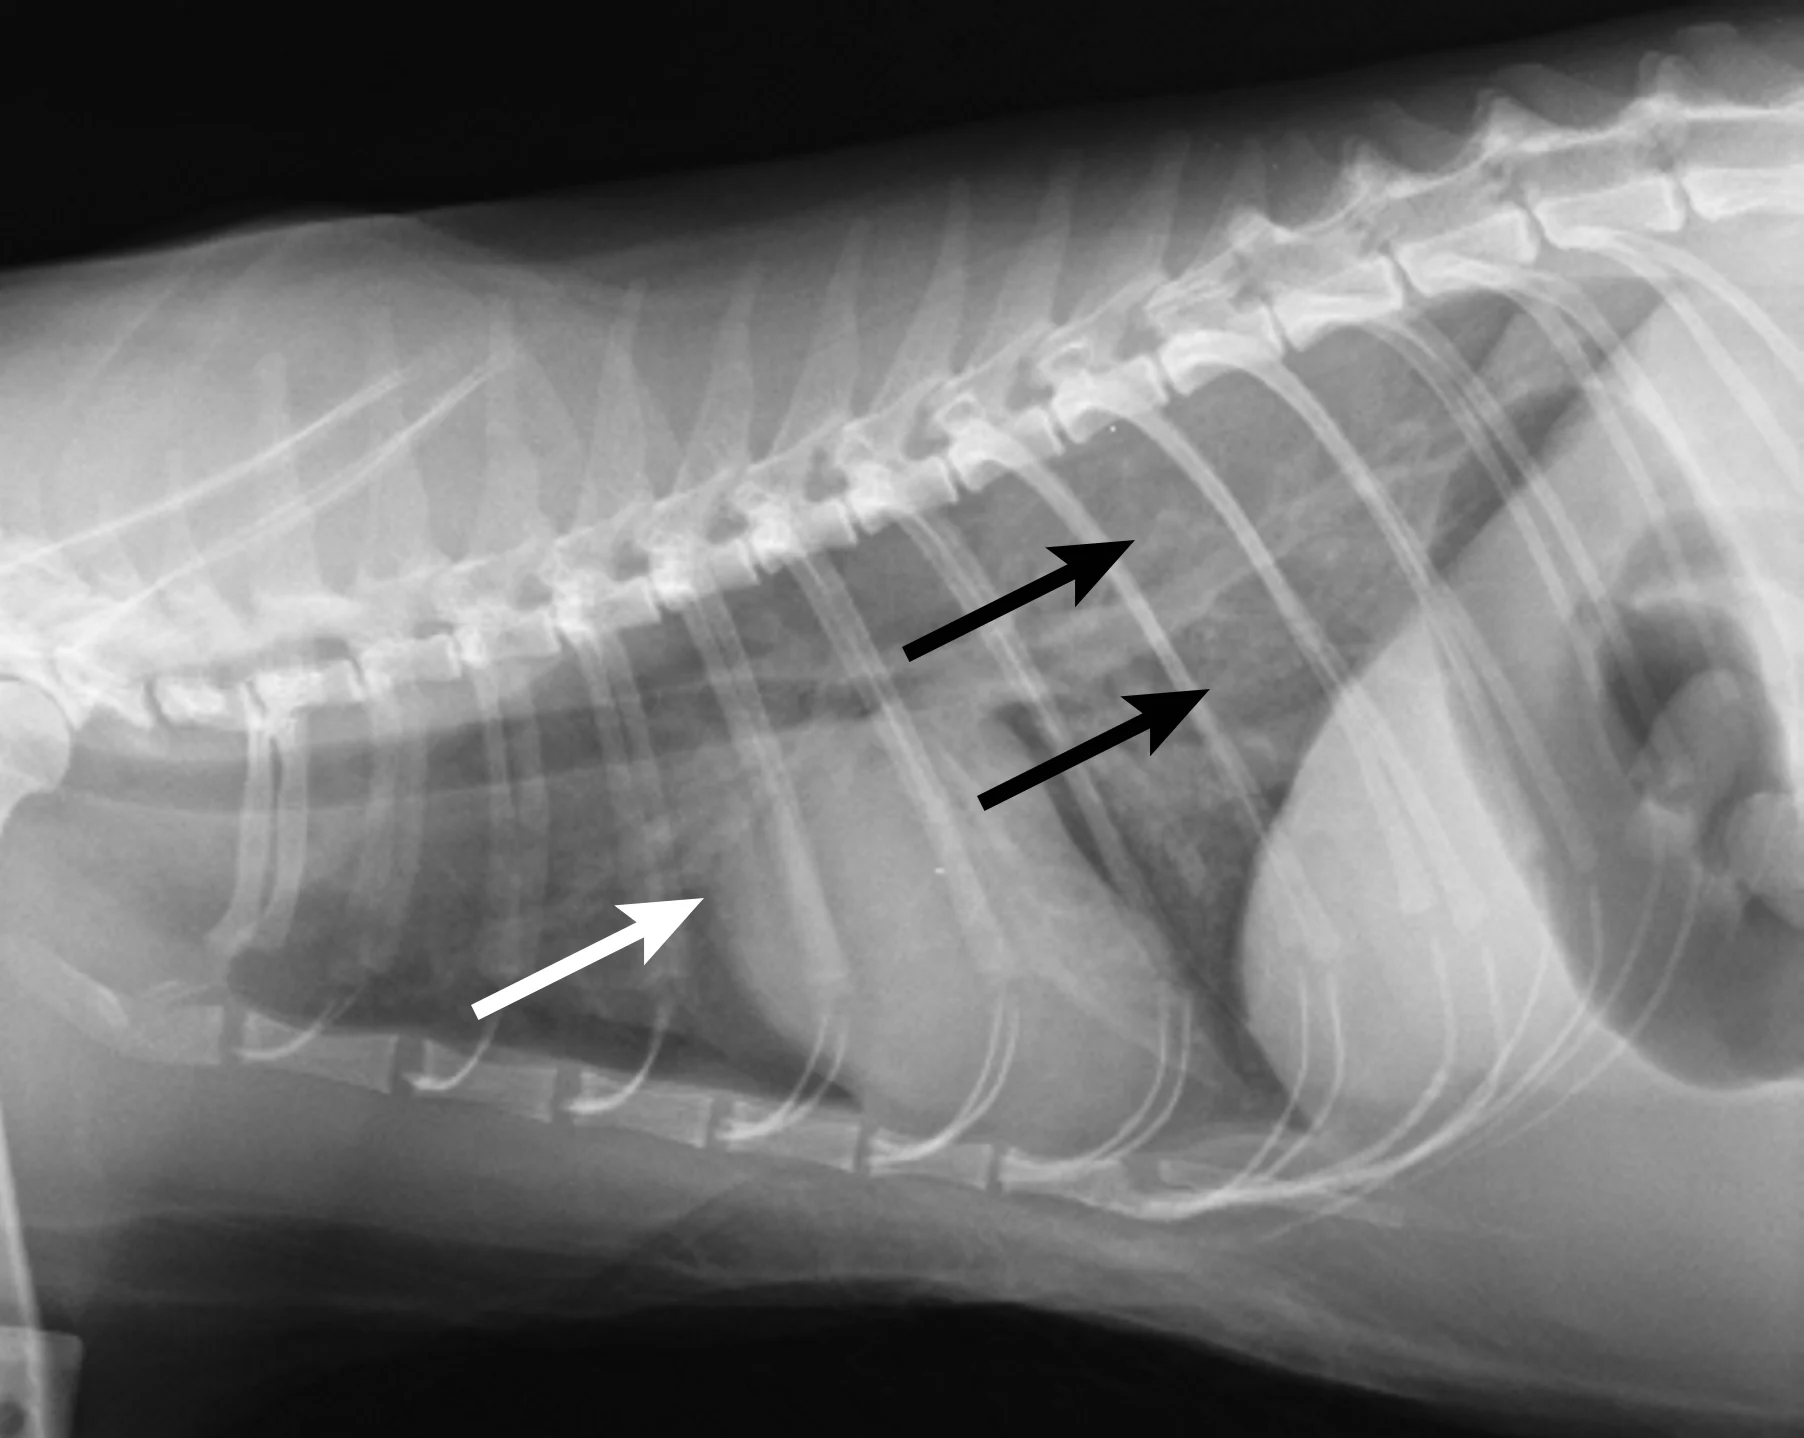

Thoracic radiography (Figure 2) revealed cardiomegaly (vertebral heart score of 8 [range, 7.2–7.8]) characterized by left atrial and ventricular enlargement, distended pulmonary veins, and a pulmonary interstitial pattern. The location of the pulmonary edema was more severe in the left lung lobe. Feline pulmonary edema may not follow the classic caudodorsal and perihilar distribution pattern noted in canine patients.

Figure 2 Right lateral (A) and dorsoventral (B) thoracic radiographs showing cardiomegaly, pulmonary venous distention (white arrows), and pulmonary interstitial densities (black arrows)